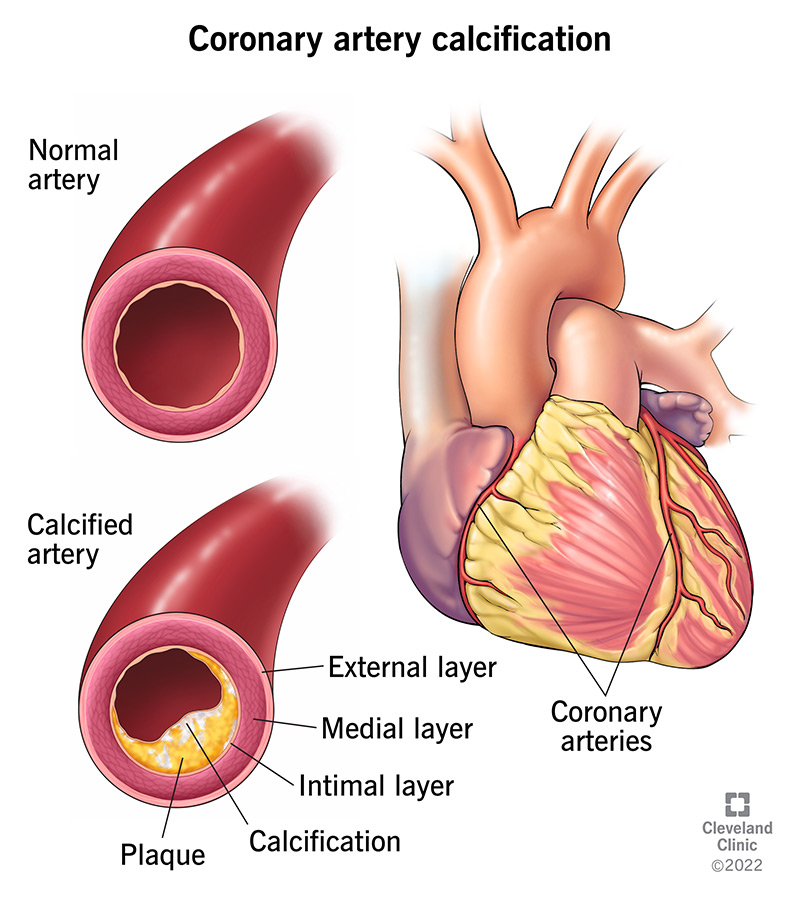

How to prevent calcium deposits. Natural treatments for calcium deposits can break down deposits, reduce inflammation and relieve pain. If you’re 65 or older, your healthcare provider may recommend. They’re common and often show up on a routine mammogram.

A great and easy way to prevent calcium buildup is by applying a calcium prohibitor or blockerto the pool tiles or glass. You may be able to prevent calcium deposits by monitoring your health and seeing your healthcare provider regularly. Let the efflorescence run its course.

You can do this by: To protect your oasis it’s essential to remove all calcium deposits. Below are a few options that break down calcium deposits.